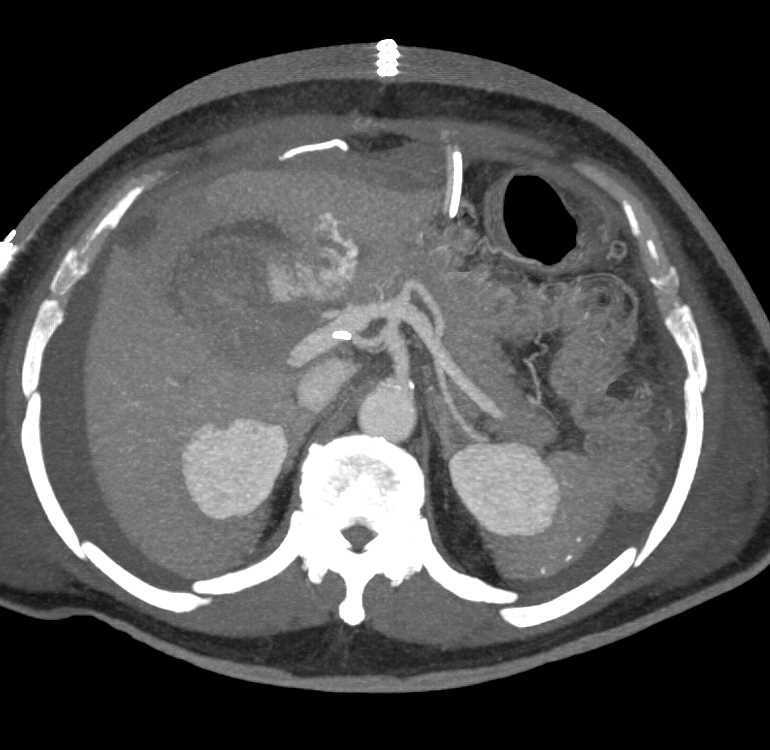

Multifocal Hepatocellular Carcinoma (Hepatoma)